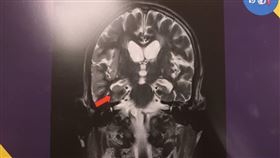

前世來過?男遊埃及「既視感」竟癲癇幻覺

疫情解封,許多民眾開始往國外跑,但有一名54歲男性,...

2023/10/17 10:36